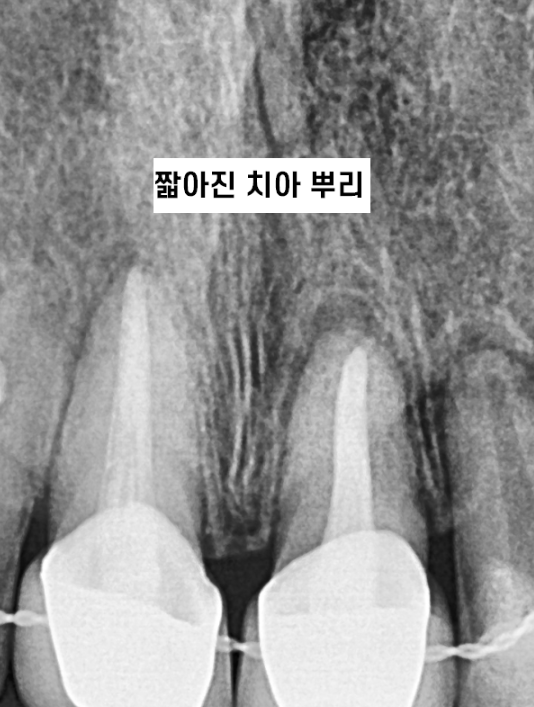

치아 뿌리를 치근이라 표현하기 때문에

치근 흡수라 부르기도 합니다.

치아 교정 부작용 중에 하나인데

치아 뿌리를 이동하는 과정에서 짧아질 수 있습니다!

잇몸 뼈 안에서 일어나는 일이기에

눈으로는 관찰이 어렵습니다!

250103 x-ray를 보고 확인하죠~

241022 겉으로는 전혀 치근흡수가 일어났는지 알 수 없어요